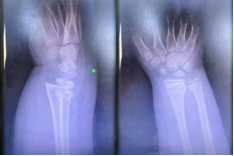

阳光讯(记者 郑亚雷 通讯员 曾雪琴)1月15日,9岁男童小洋因不慎摔伤致右腕部剧烈疼痛、活动受限4小时,被紧急送往西安市红会医院就诊。经影像学检查,确诊为右桡骨远端骨折合并骨骺滑脱,骨折类型复杂,复位难度较高。

患儿入院时携带的X线片显示,右桡骨远端骨皮质连续性中断,骨折端成角畸形,并伴有骨骺滑脱。此类涉及骨骺的儿童骨折对复位精度要求极高,既要恢复骨骼的正常解剖对位,以保障肢体功能及骨骼正常发育,又需最大限度避免对骨骺造成二次损伤,以免影响未来的骨骼生长,这给治疗带来了不小的挑战。

整个复位过程在团队的默契配合下顺利完成,术后患儿疼痛显著缓解,随即予以稳妥的外固定处理。复查X线片显示,骨折端对位对线明显改善,达到功能复位标准。安浩医生随后向家属详细交代了家庭护理要点、观察事项及康复指导,并安排次日返院复查。